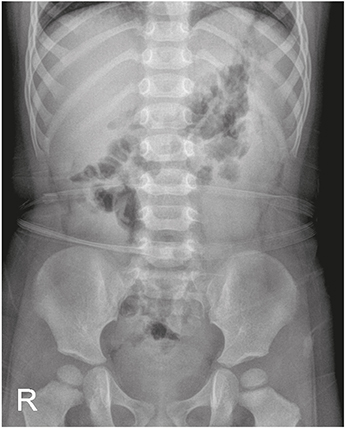

The patient was subjected to bowel sonography to exclude intussusception; with results showing no evidence of intussusception but edematous bowel wall thickening, which suggested enteritis, and a 6 mm dilatation of the appendix with wall thickening, which was suspicious of early appendicitis (Fig. 2). Intravenous antibiotics were initiated upon the suspicion of bacterial enteritis and symptomatic medication was administered for watery diarrhea and abdominal pain.

Fig. 2

Wall thickening with 6 mm of dilatation of appendix was observed on bowel sonography.